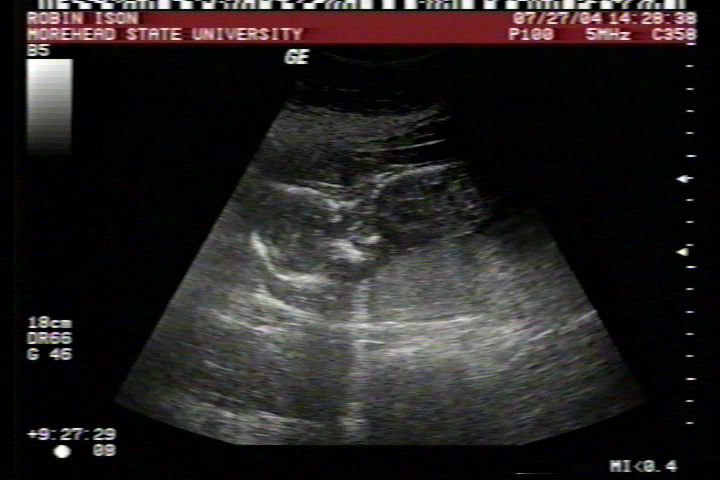

Pictures from Ultrasound at 17 weeks.